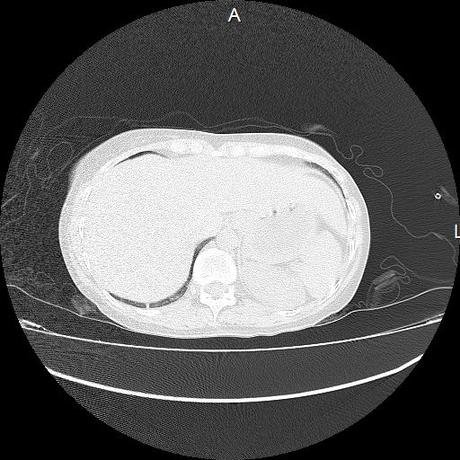

Se realiza volumen de tórax en fase simple, desde los opérculos torácicos hasta los hemidiafragmas, observándose:

El parénquima pulmonar con areas parcheadas difusas en vidrio despulido combinadas con otras areas hipodensas de baja atenuación debidas a atrapamiento aéreo y engrosamiento intersticial y zonas de fibrosis de predominio en lóbulos medios e inferiores de ambos pulmones.

Ambos hemidiafragmas sin evidencia de alteraciones.

- LOS HALLAZGOS PUEDEN ESTAR EN RELACIÓN A NEUMOPATIA INTERSTICIAL PROBABLE ETIOLOGIA HIPERSENSITIVA VS AUTOINMUNE/BACTERIANA/FUNGICA.